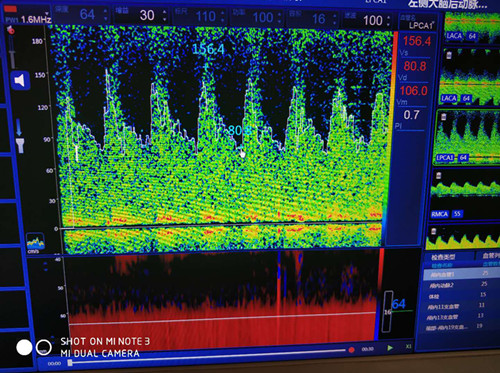

大腦后動(dòng)脈血流速度增高